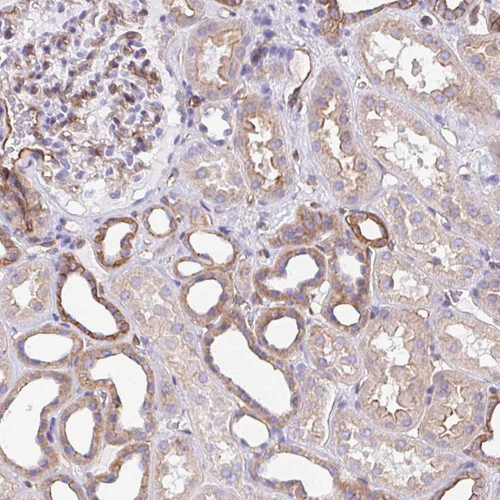

Immunohistochemical staining of human lung shows moderate cytoplasmic positivity in pneumocytes.